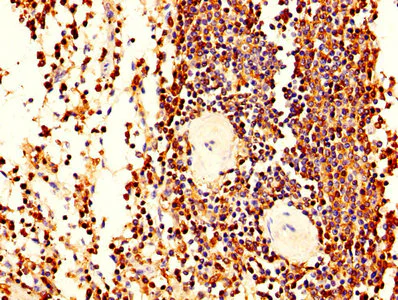

Immunohistochemistry (Formalin/PFA-fixed paraffin-embedded sections) - Anti-Plastin L antibody (AB236104)

Paraffin-embedded human spleen tissue stained for Plastin L using ab236104 at 1/400 dilution in immunohistochemical analysis.

After dewaxing and hydration, antigen retrieval was mediated by high pressure in a citrate buffer (pH 6.0). Section was blocked with 10% normal goat serum 30 minutes at RT. Then primary antibody (1% BSA) was incubated at 4°C overnight. The primary is detected by a biotinylated secondary antibody and visualized tissue using an HRP conjugated SP system.